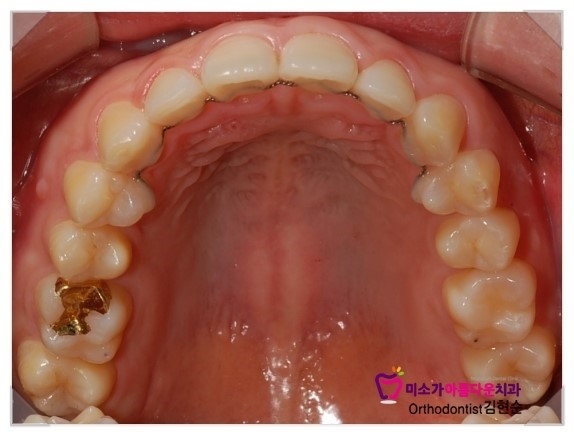

그리고 유지장치는 얇은 철사를 붙여드렸는데

치과에서 교정이 거의 끝난 분들에게 알려드리는 주의사항은

교정이 끝나면 교정기를 빼고 너무 신나서 유지장치를 잊어버리시는 분들이 많은데

치아는 교정이 끝났어도 원래 위치로 돌아가려고 하기 때문에

한동안(교정기간정도)은 유지장치를 꼭 유념해주시고

유지장치를 꾸준히 끼고 다니시다가 천천히 끼는 시간을 줄여주시는 편이 좋습니다.

치아 안쪽에 철사처럼 보이는 것은 교정이 끝나고 붙이는 교정 유지장치입니다.

교정후 교정유지장치를 하지 않으면 치아가 원상태로 돌아가기때문에 교정한 기간만큰 꼭 해주어야 합니다.